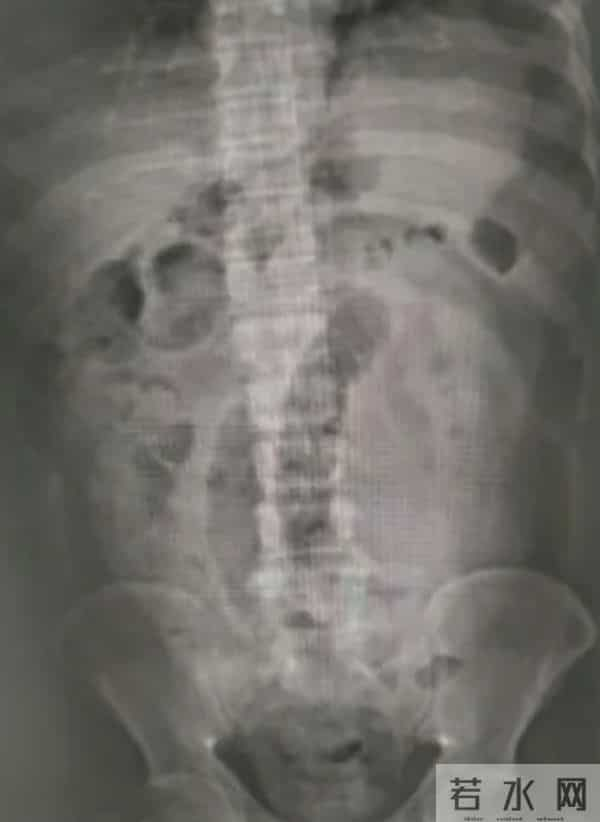

经检查

急诊医生发现张先生腹部

已出现了肠梗阻

肠梗阻不仅导致张先生肚子痉挛性绞痛,还导致无法排便和放屁。随后他被收入普通外科。